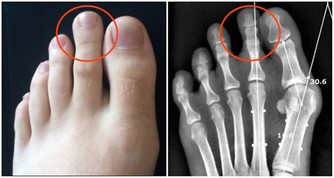

爬樓梯或爬山屬於負重運動,腰部以下的關節都要承受自己身體的重量,尤其膝蓋受力最多。

當身體爬階向上時,膝蓋負擔的重量會瞬間增為平常的4倍左右。

以一個體重60公斤的人為例:平路行走時,兩邊膝蓋各承重60公斤。

爬樓梯或爬山時,膝蓋負重瞬間變成240公斤,相當於左右膝蓋上各扛了一架鋼琴。

而且,這種對膝蓋的磨損是不可修復的!磨損如果過度嚴重,只能夠置換關節!

在爬山和爬樓梯的時候,膝關節會承受超過本身體重3到4倍的壓力。尤其是50歲以後,人的膝關節多少都會有些磨損的情況,此時,就要減少此類運動。對於有些有過膝關節損傷的朋友40歲以後就要特別注意了。